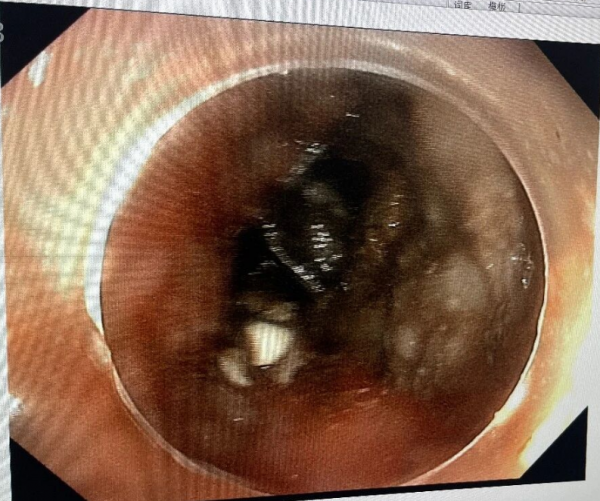

术中,张俊伟主任凭借娴熟的操作技巧,在胃镜直视下精准定位钢笔帽,利用网篮轻柔包裹异物,缓慢将其拖出。整个手术过程仅耗时15分钟,异物完整取出,患儿生命体征平稳,未出现任何不良反应。